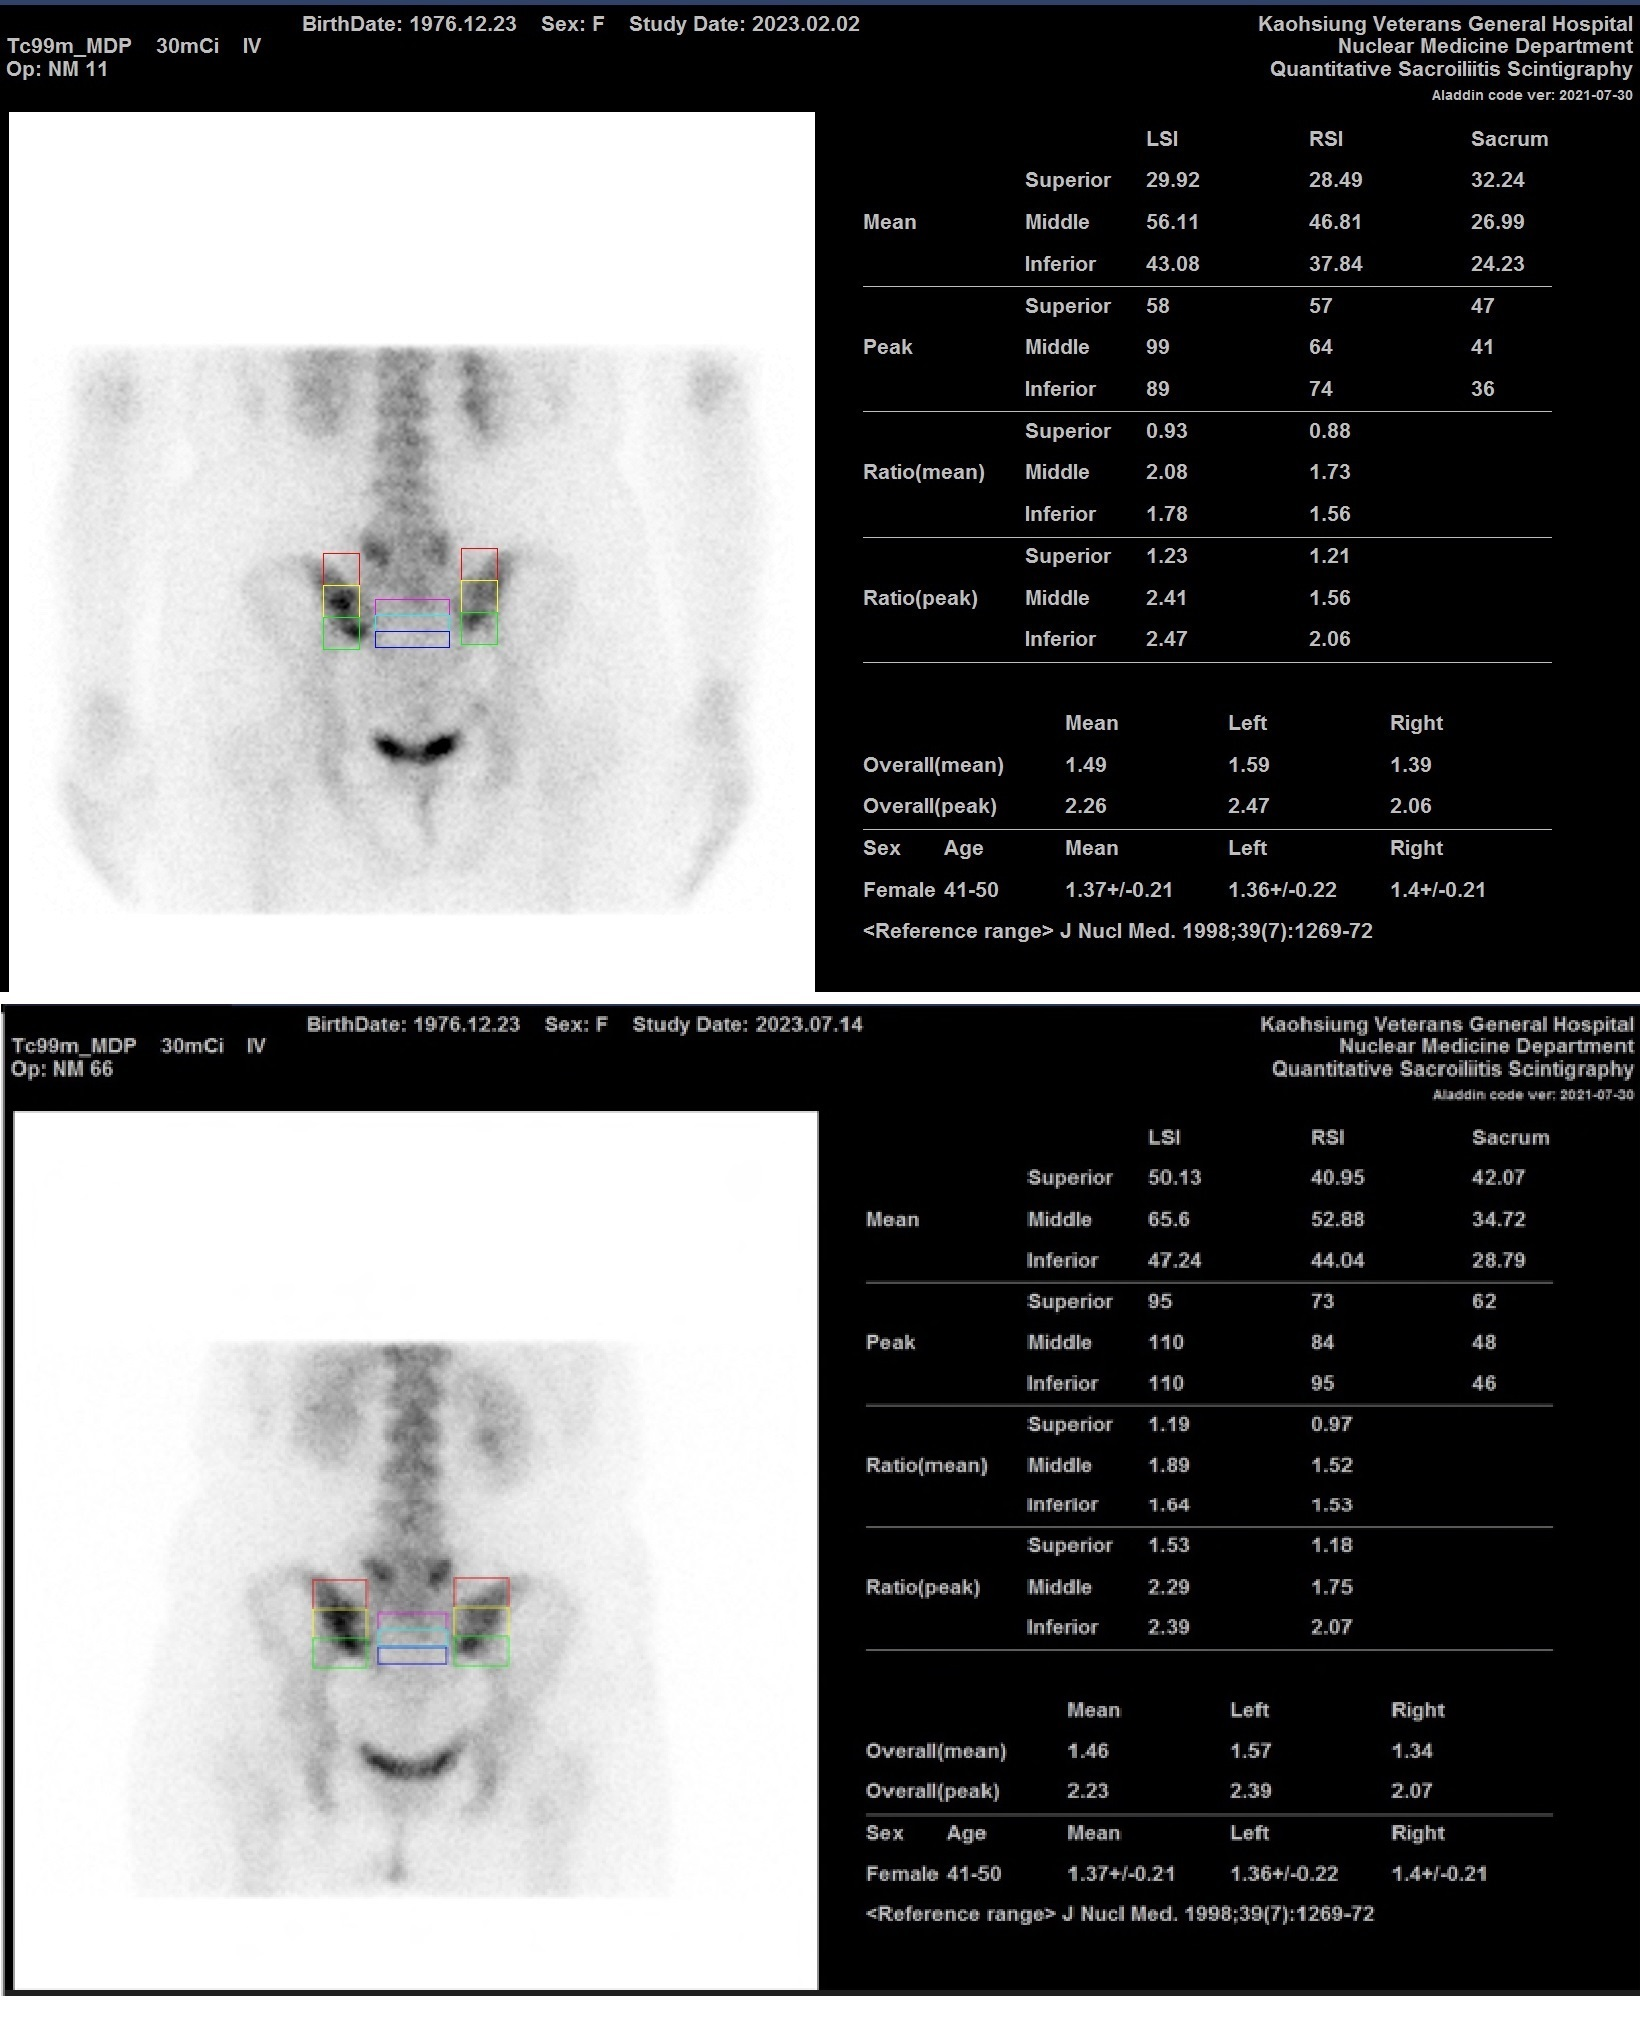

Osteitis condensans ilii (OCI) was reported first in 1926, which was also called as idiopathic pelvis sclerosis,38 or hyperostosis triangularis ilii.39 OCI often shows intermittent lower backache and associated pain on SI stress tests,40 affecting women less than the age of 40. Patients also havd SI joint tenderness with obvious lumbar lordosis.41 The features of X-ray films of OCI reveal sclerosis in triangular shape along the auricular part of the both ilia with preserved space of SI joint,42,43 mimic radiographic sacroiliitis.44 OCI can bring stress in the SI joints, resulting in piriformis muscle syndrome with further sciatica. The relationship between OCI and SI joint sacroiliitis (stress), and between piriformis muscle syndrome and sciatica, has been reported. Symptoms of OCI showed with assocaited sciatica can be effectively treated by simple injection SI joint, which use QSS as the first to detect SI joint stress prior and after the injection.45 OCI is intractable in patient with SARS-CoV-2 infection, and higher ratios of QSS persisted even after intervention of multiple rehablitation modalities (Figure 1).

Figure 1 Osteitis condensans ilii is intractable in this case with SARS-CoV-2 infection, and higher ratios of QSS persisted even after intervention of multiple rehablitation modalities before (1A) and after (1B).